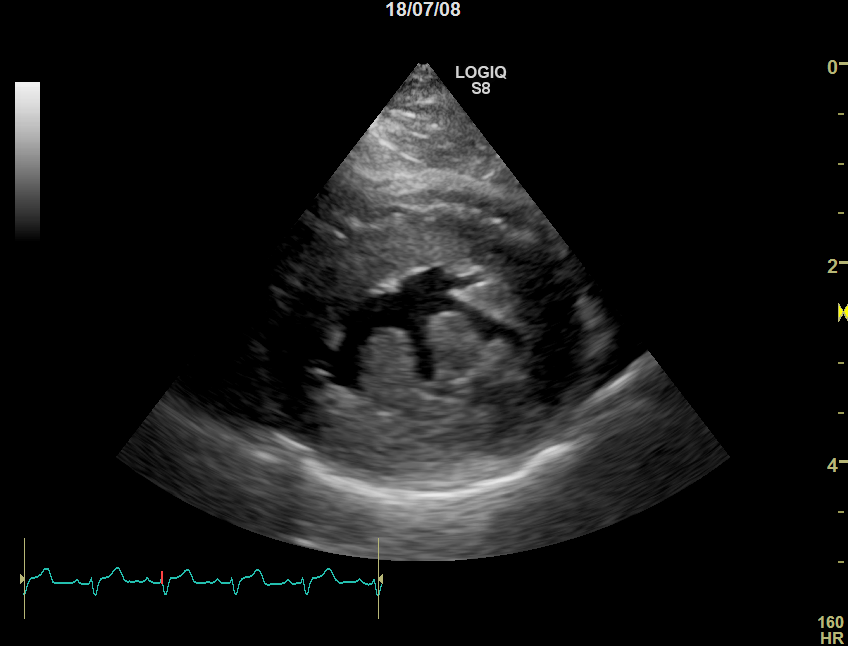

正常な猫

心臓病(肥大型心筋症)の猫

肥大型心筋症の猫では左心室の壁が厚くなり、内部が狭くなっているのが分かります。